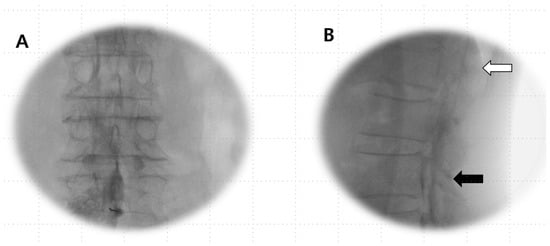

If the Tuohy needle was positioned within the subarachnoid space (Figure 3) or straddled both the subdural and subarachnoid spaces (Figure 4A–C), it was removed, and epidural anesthesia was attempted at a different level.

Figure 3.

Subarachnoid image in lateral view: a single-layer image shows a pattern of hyperbaric contrast medium in the most ventrally dependent region featuring ventral undulations attributable to the arachnoid mater when in the prone position. There is a line of lucency between the contrast spread and the posterior vertebral body, suggestive of the area pertaining to the anterior epidural–subdural space.